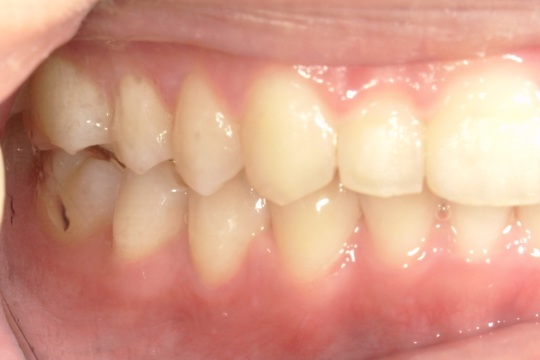

Y.S. 30代男性

全体的にガタガタしているのが気になるという主訴だったため、上下左右第一小臼歯を抜歯し、叢生を並べました。

治療の期間:R3. 9/1〜R5. 10/31

治療の価格:88万円